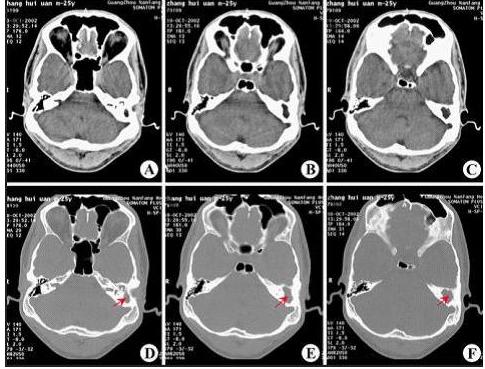

“乳突有效治疗术”祛除中耳炎乳突炎,遏制听力下降

乳突炎常继发于中耳炎,引起乳突粘膜充血及水肿,分泌物增多。继续发展可破坏气房间隔,甚至破坏乳突骨壁...[详情]

乳突炎症状表现有哪些?

乳突炎是乳突气房粘膜及骨质的急性化脓性炎症,多由急性化脓性中耳炎发展而来。据西安新城中大耳鼻喉医院...[详情]